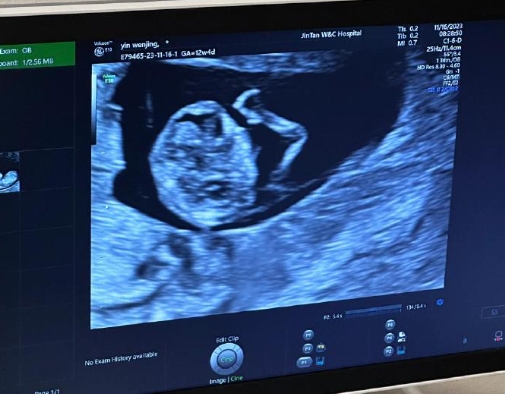

乙肝患者能否通过三代试管实现生育愿望,需结合肝功能、病毒载量及医学防护措施综合判断。非急性肝炎期且病毒控制稳定的患者,在规范治疗和严密监测下,可有效降低母婴传播风险,顺利完成试管周期。

乙肝患者可通过第三代试管婴儿技术实现生育,但需在术前进行全面医学评估,确保病情稳定。

医生会采取严格的无菌操作,降低病毒传播风险,并通过选择健康胚胎植入进一步保障胎儿安全。